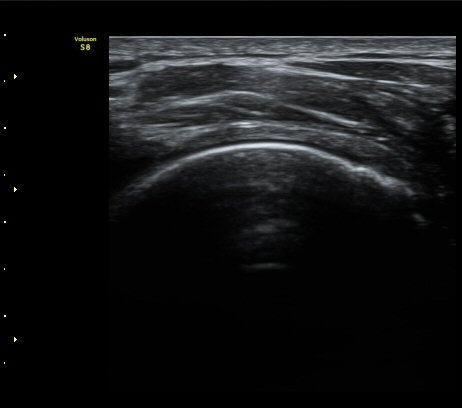

±ØÇ졂 Á¾´Ü¸é°Ë»ç¿¡¼­ ±ØÇϰÇÀº ºñ±³Àû Á¤»ó ¼Ò°ßÀ» À¯ÁöÇÔ(»çÁø 3).